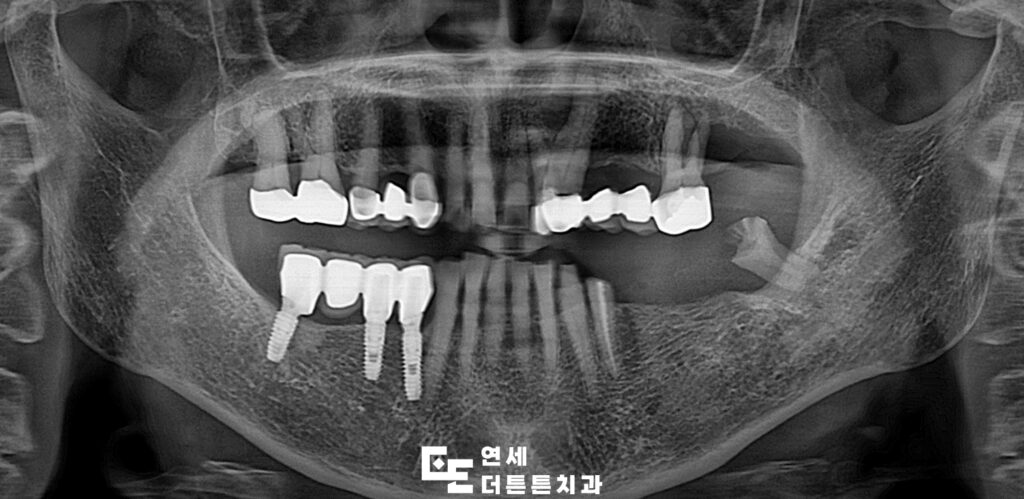

환자분께서는 왼쪽 아래 어금니가 다 빠져버리고 오른쪽으로만 식사를 하시다보니 불편하여 치료 상담을 위해 도봉동치과에 내원해 주셨는데요. 왼쪽 위에는 오래된 브릿지가 있었고 아래쪽은 상실한지 오래 되어 기능을 못하고 있는 상태로 위쪽의 브릿지를 제거하고 위, 아래 임플란트를 진행하시기로 계획을 수립하였습니다.

예후가 좋지 않은 치아는 발치 후 임플란트 식립, 살려쓸 수 있는 치아는 신경치료 후 크라운 수복으로 치료를 문제 없이 마무리하였습니다.